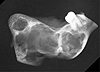

Paciente 19 anos, com lesão de crescimento lento e progressivo, deformante da mandíbula. Realizada hemi-mandibulectomia. A radiografia mostrada é referente à peça cirúrgica.